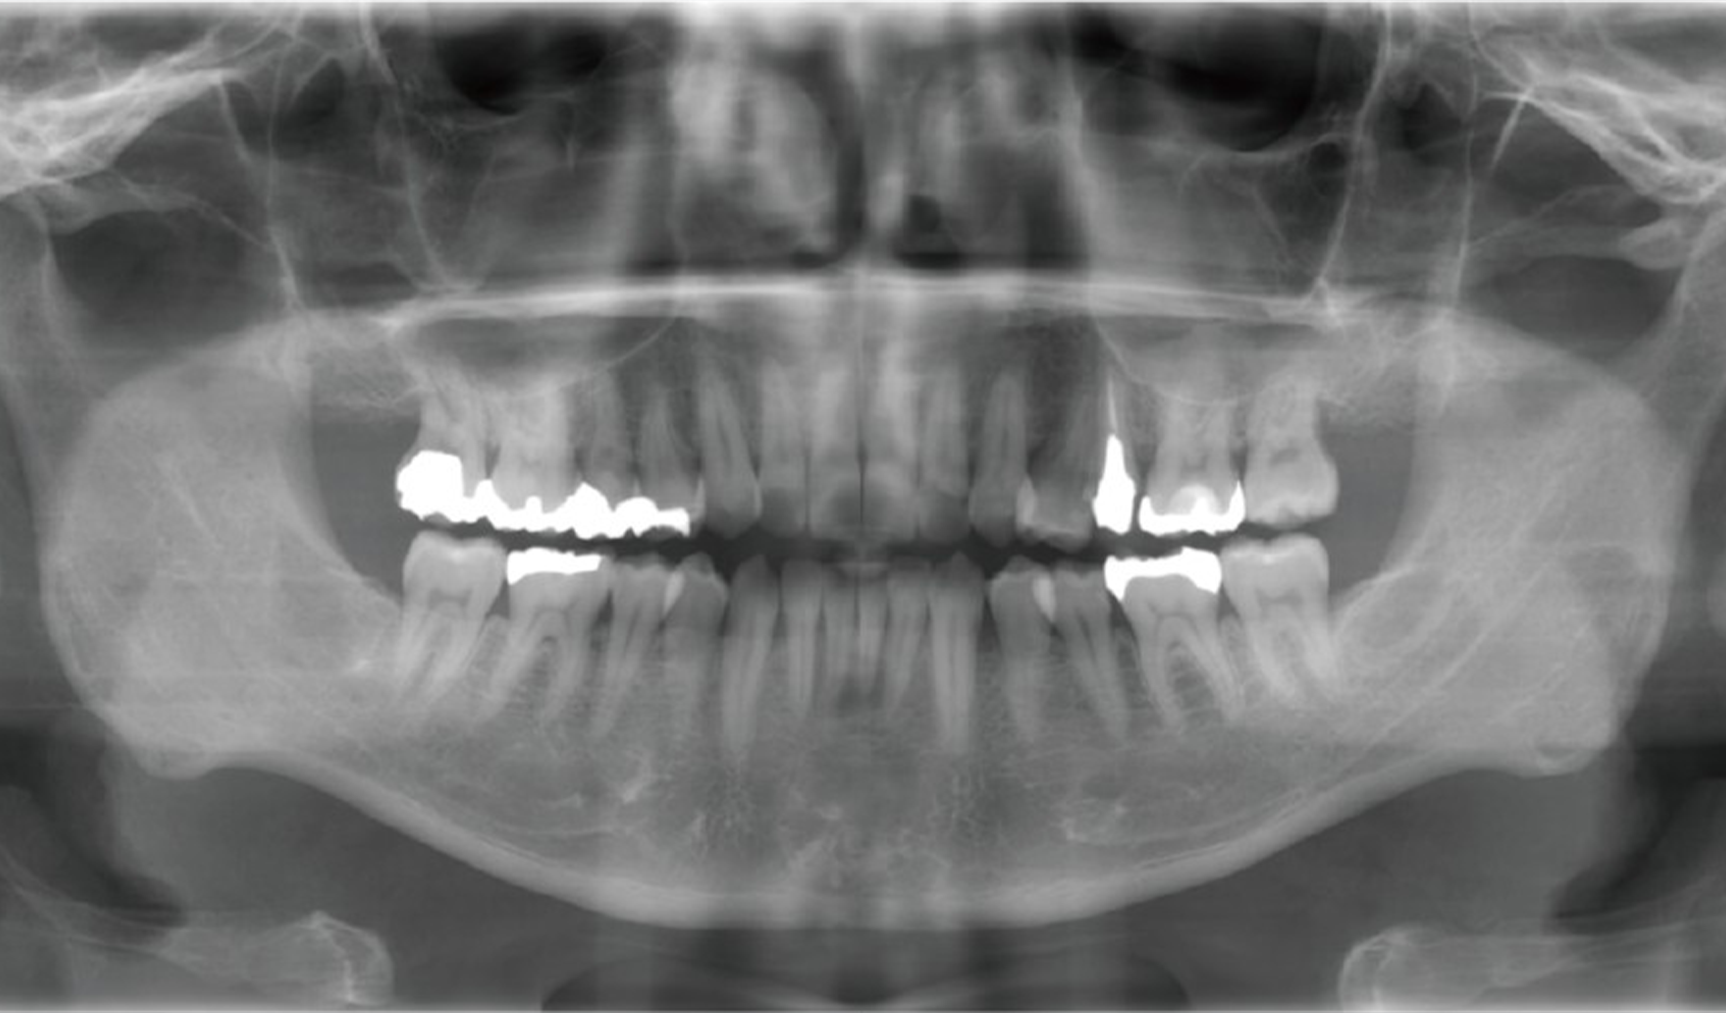

駒沢よしや矯正歯科では、より正確で安全な診断を行うために歯科用CT(コンビームCT)を導入しています。この技術により、従来のエックス線写真では得られない詳細な情報を確認し、患者さま一人ひとりに治療計画を立てることが可能です。

歯科用CT(コンビームCT)は、歯や顎骨、神経、血管などを三次元(3D)で映し出すことができる画像診断装置です。

- 親知らずの抜歯や埋伏歯の診断

- 顎関節症の診断

- 骨の成長や形態の詳細な確認

- インプラント治療を検討している場合

安心・安全な検査環境で、正確な診断と効果的な治療計画を。7 歯科用CT

歯科用CTで得られる情報

顎骨や歯の詳細な構造

骨の密度や形状、歯根の位置などを正確に把握します。

歯の埋伏や異常の確認

親知らずや埋伏歯の位置を詳しく診断します。

神経や血管の位置の確認

矯正治療や外科処置において、神経や血管を傷つけないよう計画を立てます。

病変や異常の発見

顎の中に隠れた病変や異常を早期に発見することが可能です。

歯科用CTのメリット

診断の精度向上

平面のエックス線写真では見えなかった部分も3D画像で確認できるため、診断の精度が格段に向上します。

治療の安全性を確保

歯や顎骨の状態を立体的に把握することで、安全かつ効果的な治療が可能です。

患者さまへのわかりやすい説明

3D画像を使って治療計画を説明するため、患者さまも自身の状態をより理解しやすくなります。

駒沢よしや矯正歯科の歯科用CT

当院では、歯科用CT機器を使用して、放射線量を最小限に抑えた安全な撮影を心がけています。短時間で撮影が完了するため、患者さまの負担も軽減されます。

歯科用CTが必要なケース

安心して治療を受けられるために

駒沢よしや矯正歯科では、歯科用CTを活用して精密な診断と治療計画を提供しています。